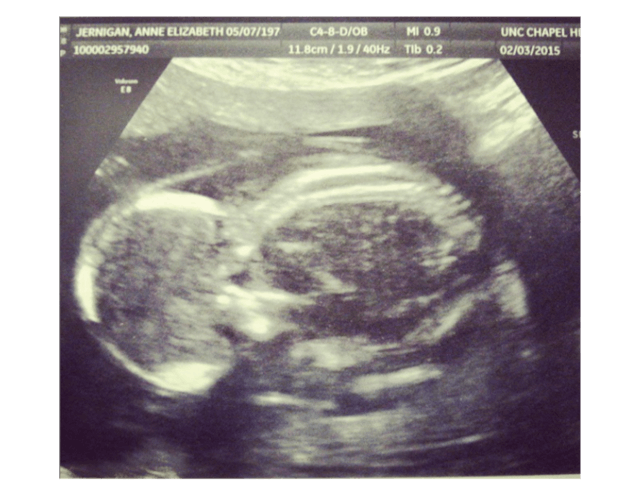

When they learned they were pregnant with their first girl, Vivianne, they were “over the moon,” said Elizabeth. But at 12 weeks, doctors told them Vivianne had Trisomy 18 and was “incompatible with life.”

The couple met with pro-life doctors who care for children with Trisomy 18, and made plans to provide Vivianne with care rather than let her die. But sadly, during an ultrasound at 18 weeks and 5 days, they learned Vivianne no longer had a heartbeat.